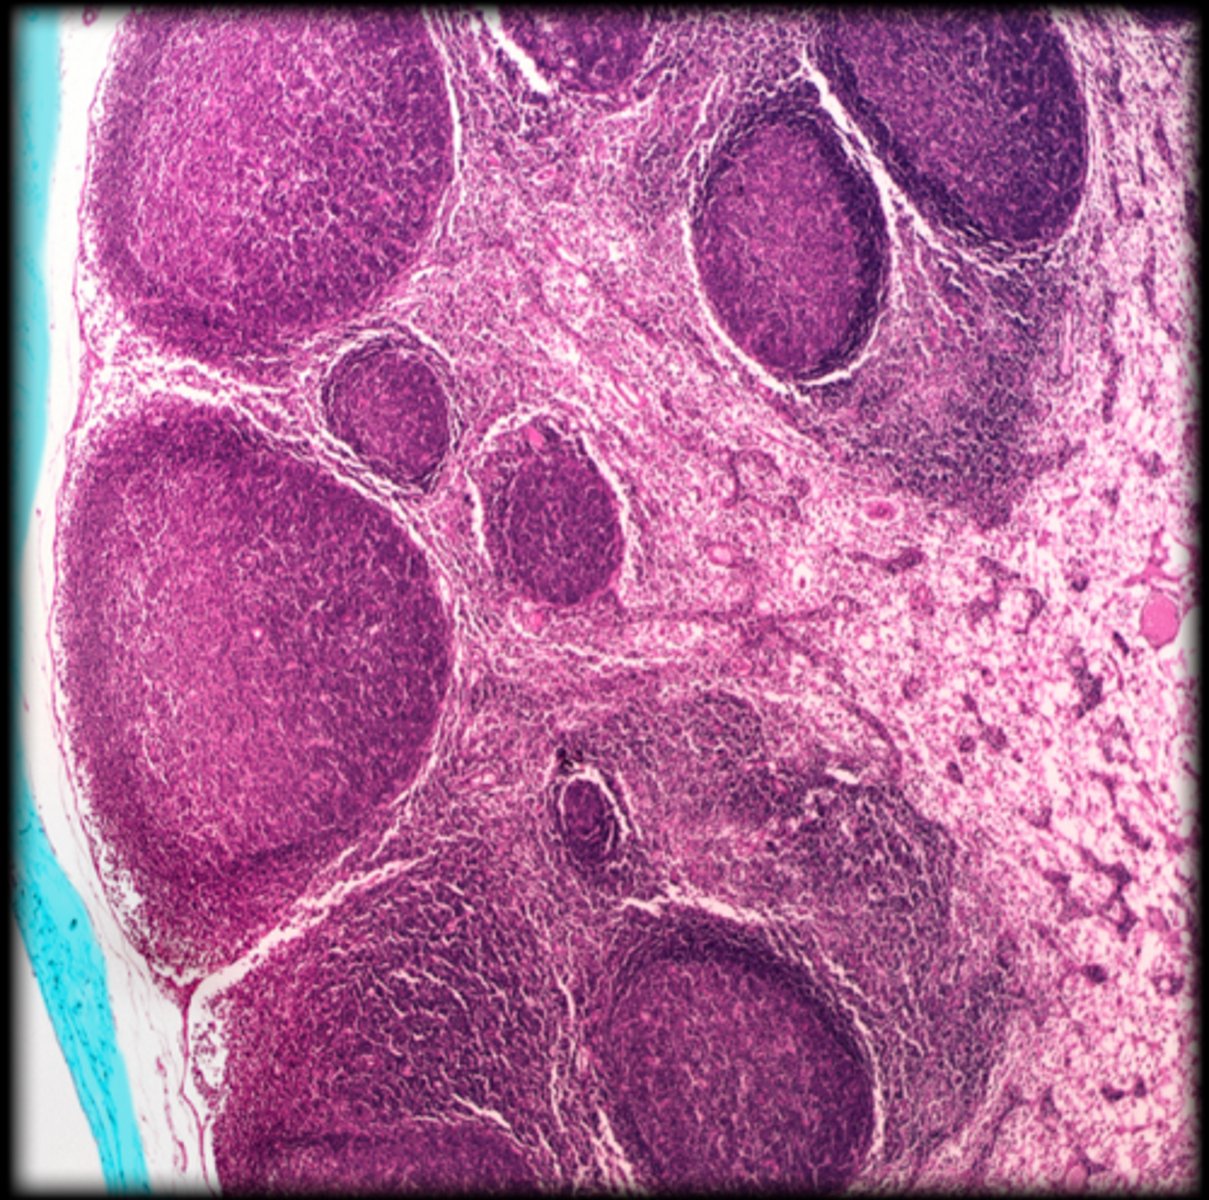

cortex

Fetal thymus

medulla

hassall's corpuscle

Thymus